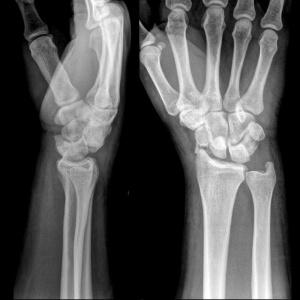

Для диагностики недостаточно визуального осмотра травмы, тут необходима рентгенография. Только так врач сможет внимательно изучить поврежденную область и назначить правильное лечение.

Также при более тяжелых случаях может оказаться нелишней компьютерная томография лучезапястного сустава. Серия снимков в различных срезах не оставит у врача никаких сомнений о характере повреждения.